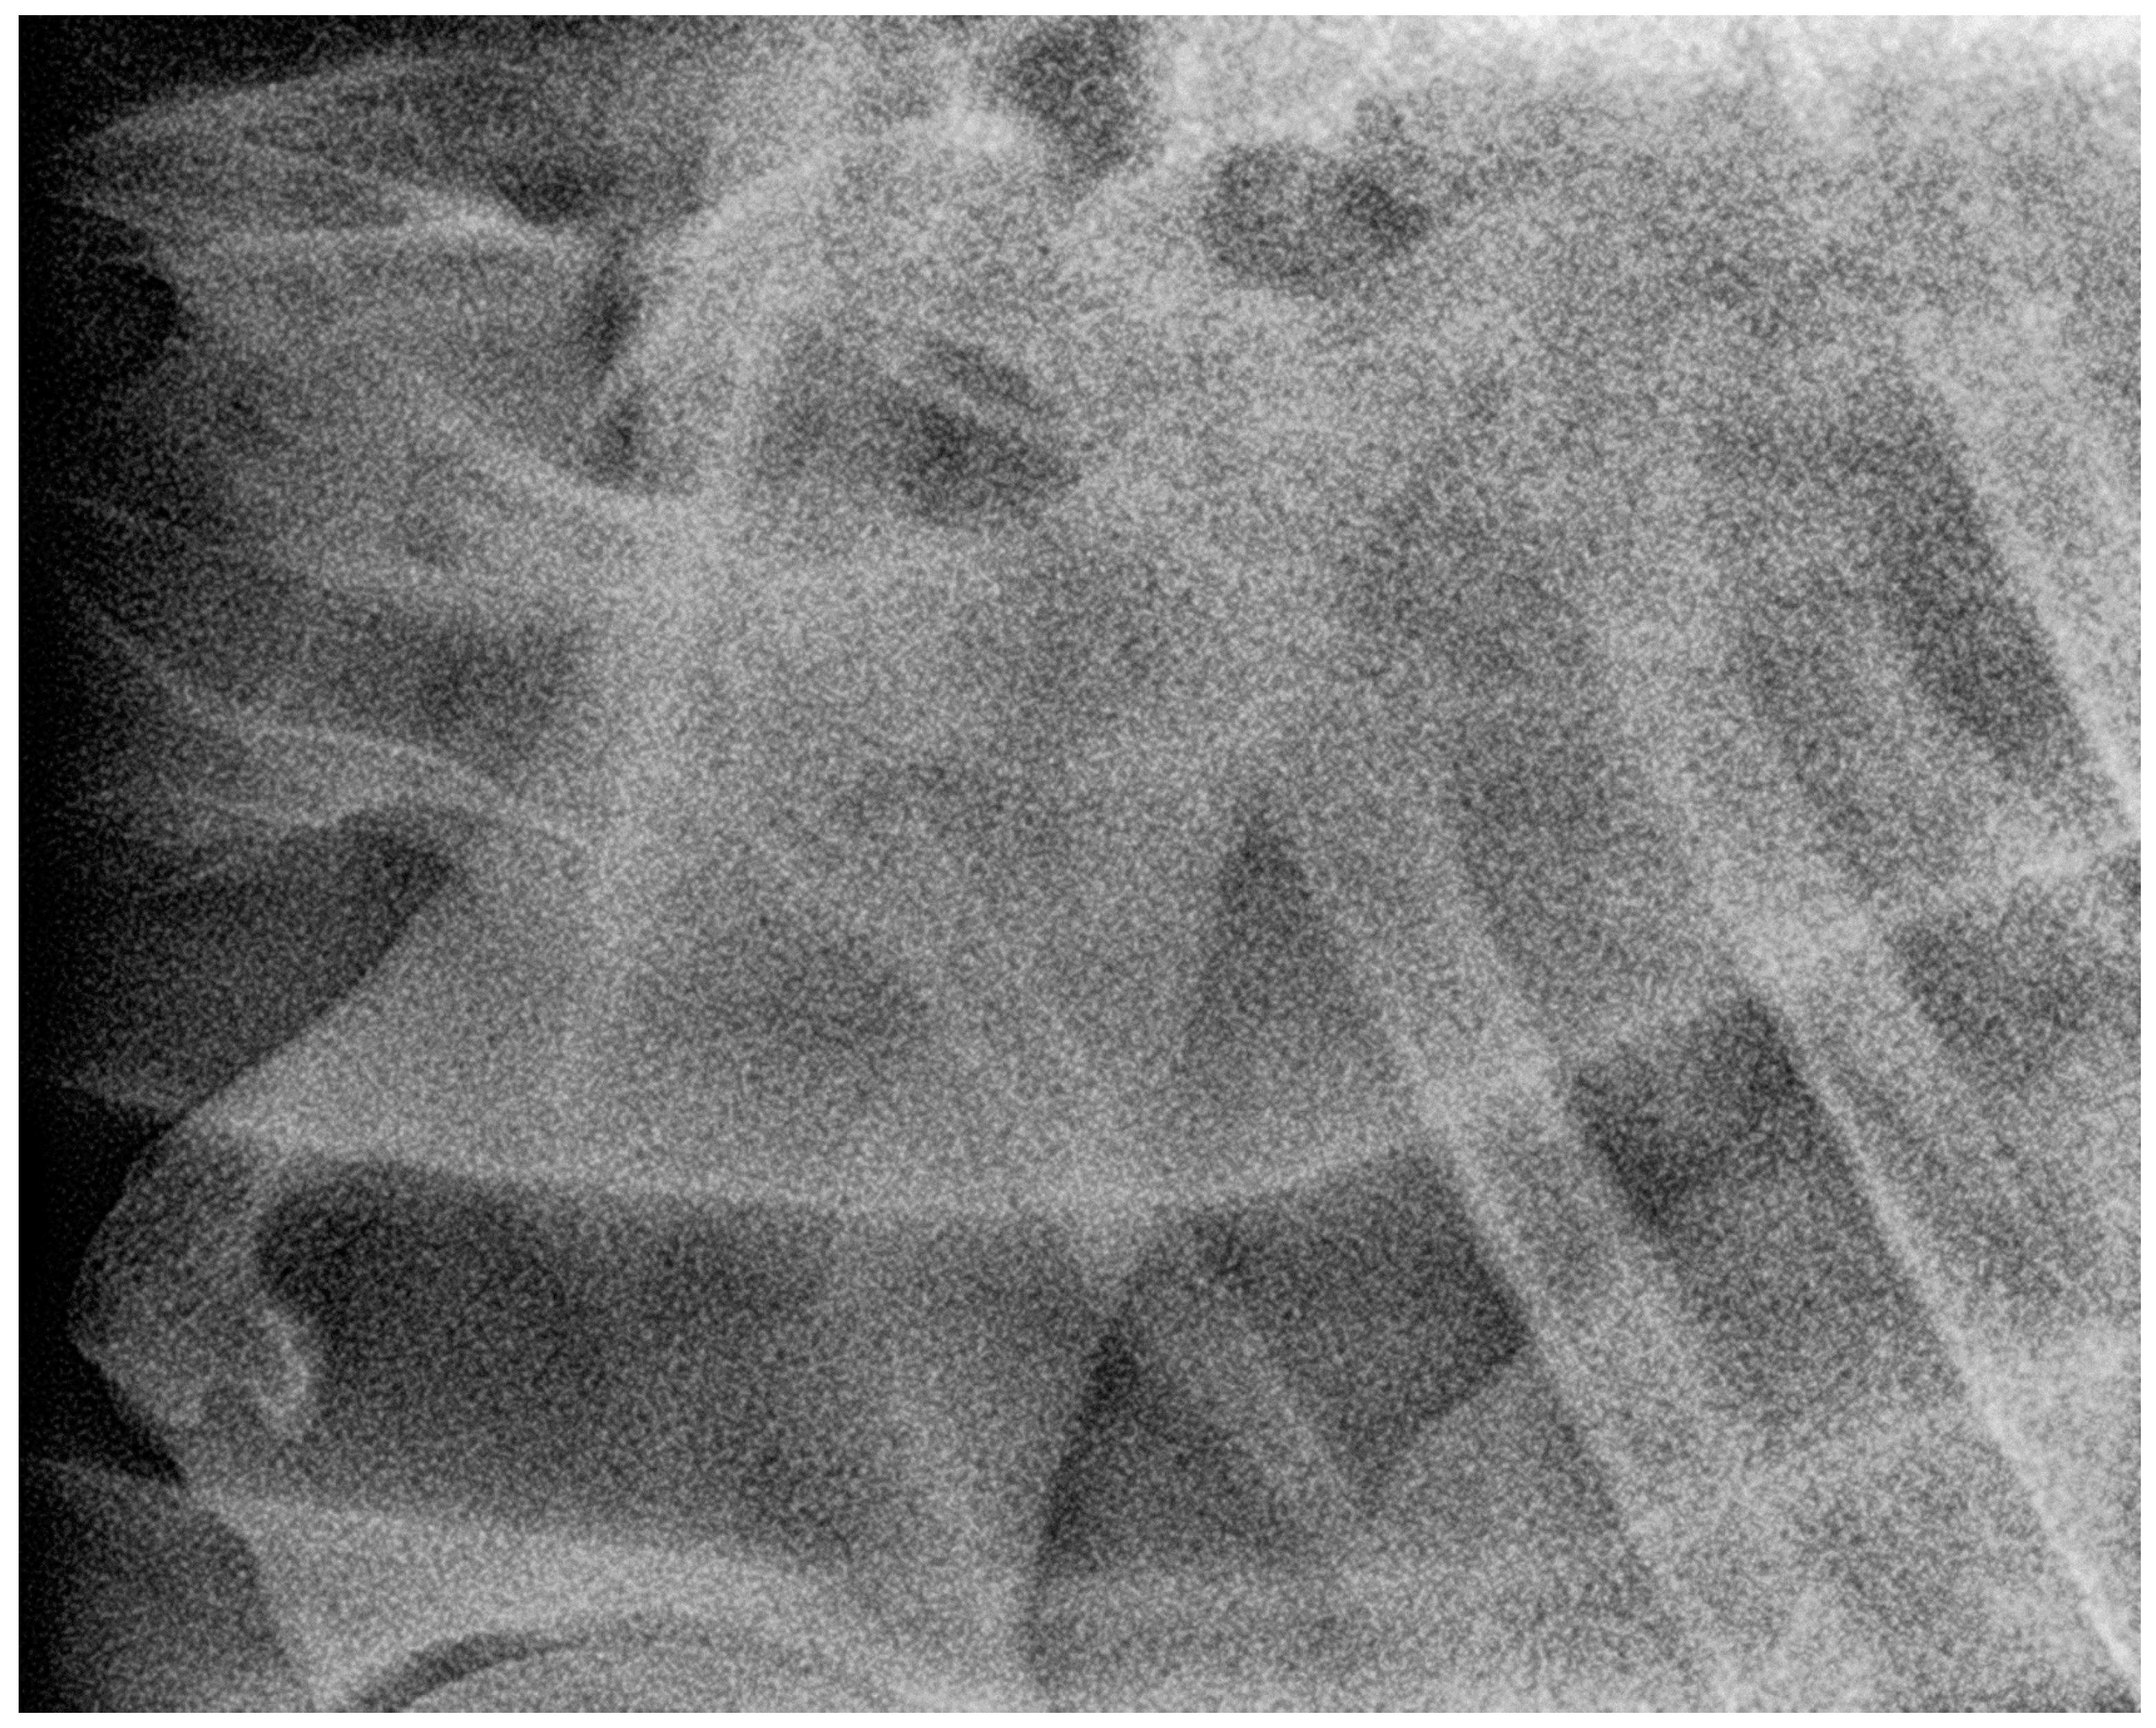

2.3. Radiographic Method

2.4. Classification System